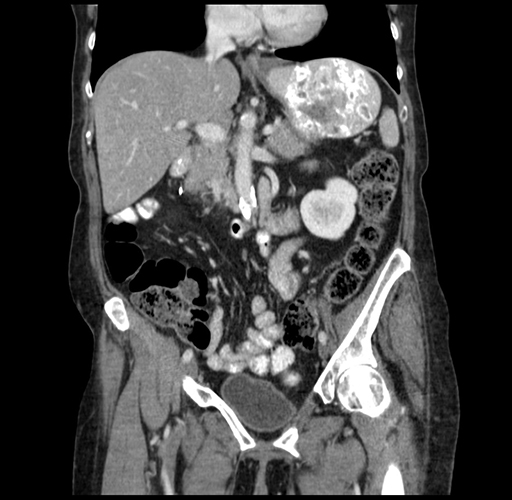

Pre-Chemo: Coronal Venous

Coronal Venous